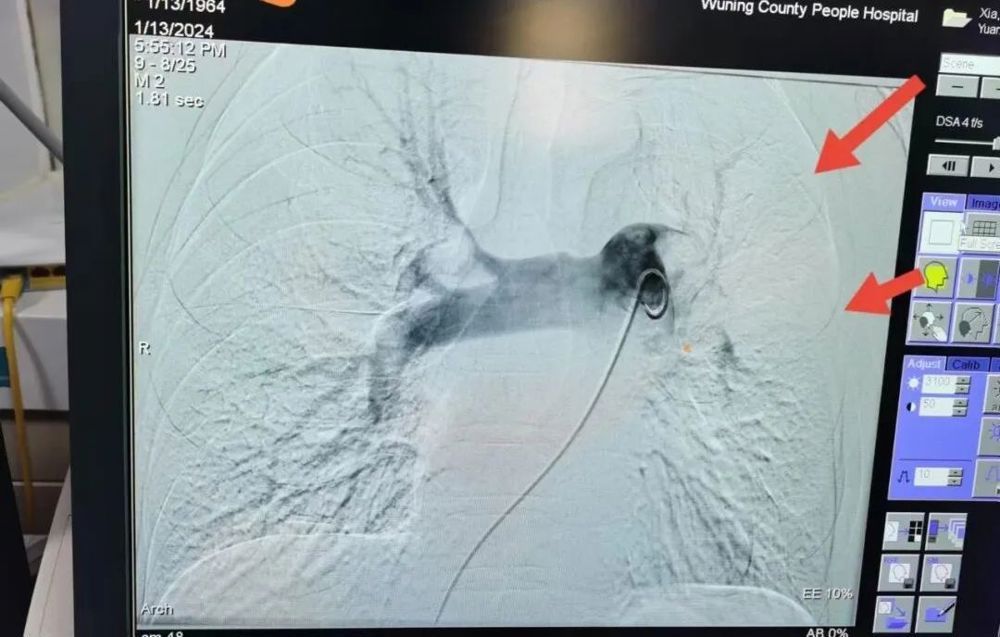

▲肺動脈造影提示(shì)左肺血管(guǎn)大片無顯影

患者夏某某,因胸悶2天(tiān)入(rù)院,曾(céng)在當地衛生(shēng)院(yuàn)檢查,未明確診斷,治療效果不佳,於2024年1月10日夜間來武寧縣人民醫院急(jí)診科(kē)就診,急診科醫師經過(guò)查體及完善心(xīn)電圖相關(guān)檢查後,發現患者血氧飽和度僅在85%,血象檢查發現血漿D-二聚(jù)體明顯升(shēng)高,血氣分析(xī)提示I型呼吸衰竭,將心電圖及檢查報告發至醫院胸痛綠色通道聯絡群中,經胸痛中心(xīn)值班醫師李露紅(hóng)分析後考慮患者肺(fèi)栓塞可能性大,立即完善肺動脈CTA檢查,檢查(chá)提示:“左右肺動脈及葉、段、亞段彌漫性肺動脈栓(shuān)塞,考慮患者大(dà)麵積肺栓塞”。李露紅醫師立即為患者予以抗凝、溶栓治(zhì)療,並為患者行肺動脈取栓術,患者(zhě)術後呼吸逐漸平穩,胸悶症(zhèng)狀有(yǒu)明顯(xiǎn)緩解,無吸氧情況下血氧飽(bǎo)和度恢複至96%。